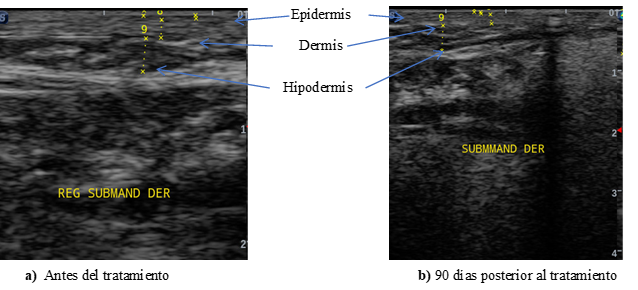

Ahora bien, para comparar los cambios ecográficos a nivel del grosor de la piel, los tejidos de soporte y la disminución del tejido adiposo, se muestran en las figuras 1 y 2, donde se puede evidenciar el aumento en grosor de la dermis-SLEB y los cambios del tejido celular subcutáneo, mediante la imagen ecográfica.

Figura 1. Evaluación ecográfica comparativa de la región submandibular derecha

En este estudio, ecográficamente se evidenció aumento del grosor de la dermis, asociado a mayor ecogenicidad de dicha capa en los controles ecográficos, siendo más evidente a los 90 días, pero se registraron incluso a partir de los 30 días posterior al tratamiento, lo cual se puede explicar por un incremento en el número de fibras de colágeno en la dermis en todos los pacientes tratados, éste efecto fue obtenido en una única sesión de endolaser, todos estos cambios pueden ser indicativos de que el tejido experimenta tensión, respaldando la actuación de soporte de la piel.

Asimismo, se evaluó la SLEB, un marcador ecográfico asociado al fotodaño y cronoenvejecimiento. Mientras estudios previos como el de González y Ollarves16 reportaron su disminución con láseres no ablativos, este estudio representa el primer registro de reducción significativa de la SLEB tras tratamiento endoláser facial con diodo de 1470 nm, con resultados visibles desde los 30 días y más notorios a los 90 días, especialmente en la región submentoniana. Esta disminución podría correlacionarse con el engrosamiento dérmico observado y el aumento de la ecogenicidad general, dados los cambios en el comportamiento acústico del tejido cutáneo tras el tratamiento.

Respecto al tejido celular subcutáneo, se evidenció una mayor ecogenicidad hipodérmica en todos los casos, especialmente en zonas como los jowls y la región submentoniana. Este hallazgo sugiere una reorganización tisular relacionada con la licuefacción de grasa y la mayor expresión de septos fibrosos, junto con la disminución del grosor adiposo.